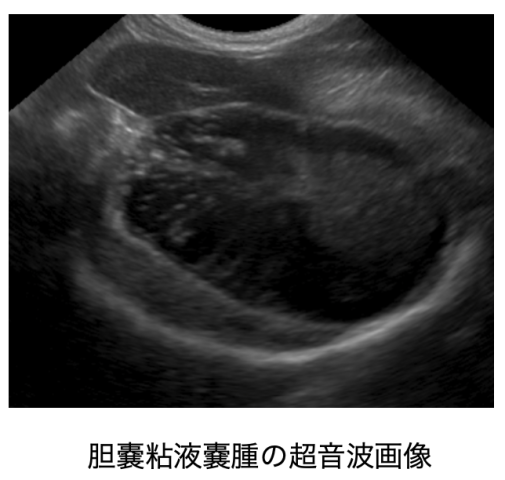

④胆嚢粘液嚢腫(たんのうねんえきのうしゅ)

胆嚢内に粘液様物質であるムチンが貯留した状態を胆嚢粘液嚢腫と言います。胆嚢粘液嚢腫の詳しい原因は不明ですが、胆管閉塞や胆嚢壊死による破裂を引き起こし命に関わることがあります。診断は超音波検査で行います。症状がなく、偶発的に見つかることも多々あります。